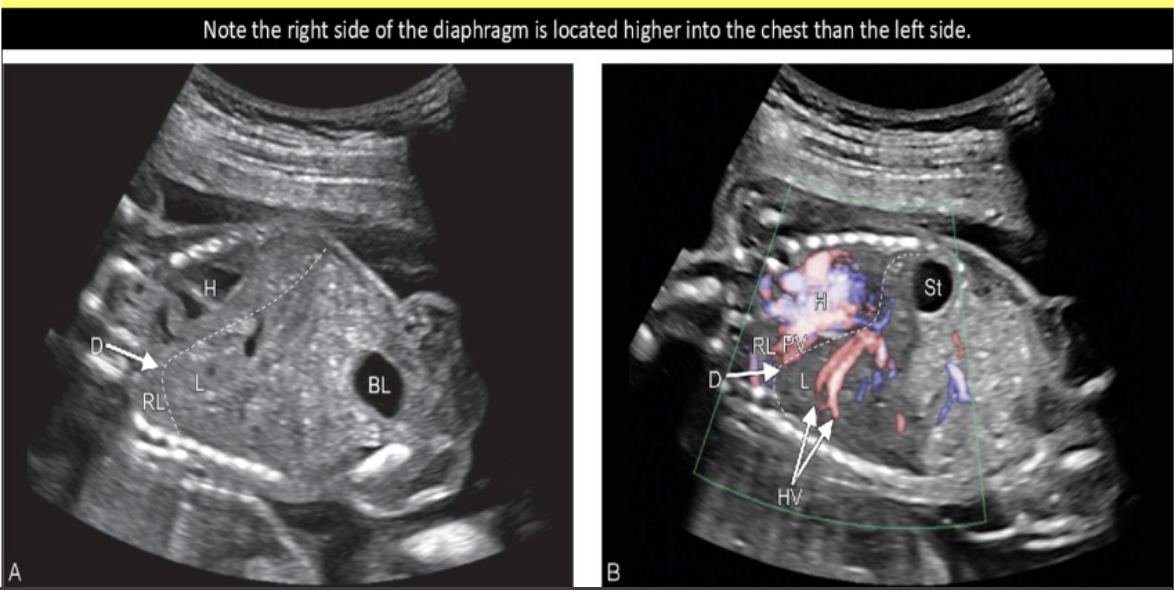

which fetal abn mimics the sono appearance of diaphragmatic hernia

.

a) situs inversus

b) situs solitus

c) duodenal atresia

d) [diaphragmatic] eventration

d) eventration